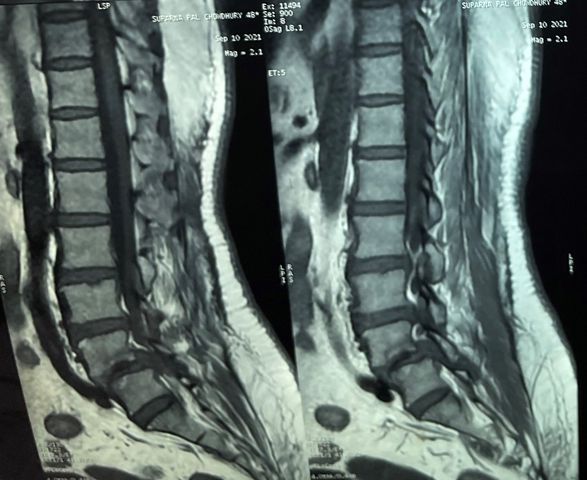

This is one of my early IPGMER days total knee replacement (tkr) surgery done on the right knee for grade 4 osteoarthrosis with medial tibial deficiency that was counteracted with bone graft held with screws. This post would be incomplete without gratitude to Dr. Debasis Mukherjee and Dr. @Chetan Chetan